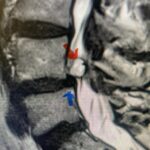

A 37-year-old male police officer complained of a one-month history of difficulty with his balance and leg weakness. He complained of achiness in his legs. He also complained of bilateral arm weakness and numbness of his hands. He was also having difficulty writing due to the weakness. Patient had an MRI of the cervical spine which demonstrated a disc/osteophyte at C56 causing spinal cord compression and concurrent myelomalacia (Fig. 3). Patient underwent an anterior cervical discectomy with a cage and plate (Fig. 4). He tolerated the procedure well with improved numbness and weakness. This is a young person with fairly extensive myelomalacia and a fairly rapid development of symptoms. For this it was felt surgery was indicated. How he will do will depend on how much of his symptoms was caused by the compressive component or intrinsic damage to the spinal cord. As a rule, patients generally improve to some extent quickly; but their recovery of their spinal cord function can sometimes take up to 2 years to realize the extent of their improvement. Patients have to be patient with themselves in terms of their expected recovery.

Fig. 3: Sagittal T2-weighted cervical MRI demonstrating a significant disc osteophyte complex causing spinal cord compression at C 5 6 with extensive myelomalacia (red arrow)